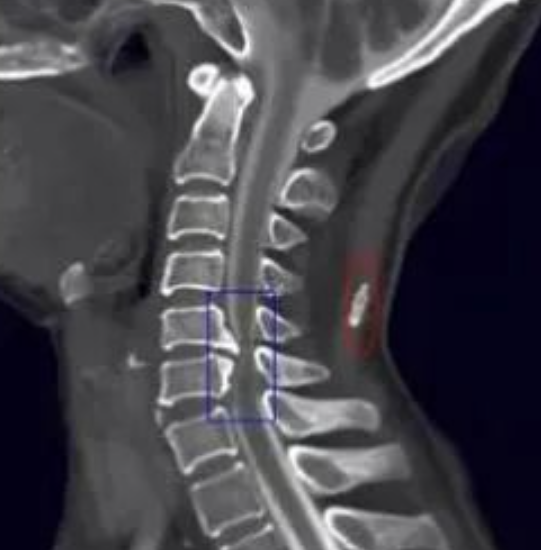

死骨和肿瘤骨有什么不同!

找到这些影像征象,复杂的骨肿瘤迎刃而解

骨肿瘤的基本影像学征象是构成骨肿瘤最基本的元素,无论多复杂的骨肿瘤都由一个或几个基本影像学征象构成,对其透彻理解和准确把握是正确诊断骨肿瘤的重要前提。